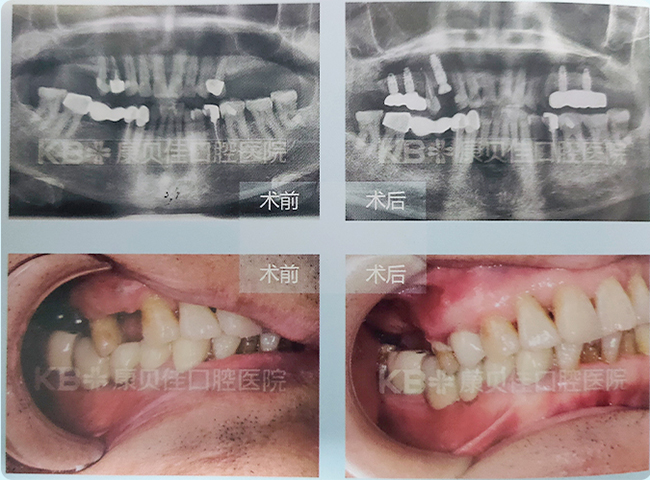

马先生 79岁

上颌双侧后牙陆续缺失,长达20余年,吃饭根本使不上劲。患者到院即要求艾斯纳博土帮他种植恢复咀嚼功能。左上通过种植2颗即刻恢复4颗牙,右上拔除松动的4号牙,植入3颗种植体,达到恢复咀嚼的效果。 现今患者已经戴_上好牙,上下后磨牙都可以咀嚼吃饭,非常开心。

右上种植3颗种植体 左上种植2颗种植体